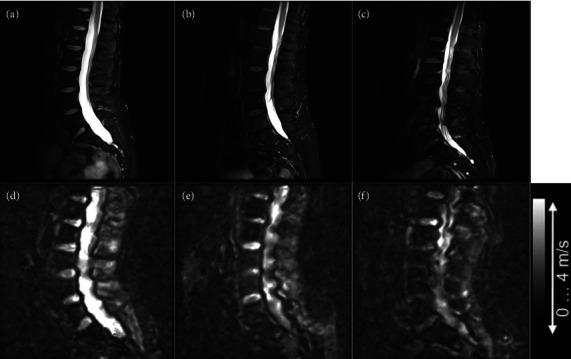

Background: Degenerative disk disease (DDD) is a progressive condition that occurs when the intervertebral discs (IVDs), which act as shock absorbers between the vertebrae, degenerate or wear out. Due to this degeneration process, the mechanical properties of the IVD, providing flexibility between adjacent vertebrae, can change. Thus, assessing these mechanical properties may improve diagnosis and treatment guidance for DDD. In this article, we tested in vivo multifrequency magnetic resonance elastography (MMRE) of the human IVD in identifying progressively DDD in three asymptomatic male volunteers aged 32, 50, and 60 years. Methods: MMRE of the lumbar spine was acquired using a dual-actuator setup and operated at four frequencies from 60 to 90 Hz. MMRE data were postprocessed using multifrequency wave-number recovery (k-MDEV) inversion algorithm. The resulting shear wave speed (SWS) values were used as a surrogate parameter of tissue stiffness and then compared to Pfirrmann grading (Pf) of disc degeneration (1-5) performed by an experienced MRI spine researcher. Results: Morphological Pf demonstrated an inverse relationship between increasing IVD stiffness and progressive IVD degeneration by a Spearman's rank correlation coefficient of ρ = -0.792, p < 0.001. Conclusion: MMRE allows measurement of in vivo mechanical properties of IVDs and may provide additional information in disc degeneration beyond standard morphological changes. Prior to the clinical use of this technique, future studies should be conducted to evaluate the reproducibility and repeatability of spinal MMRE in the spine, and particularly its potential confounders.